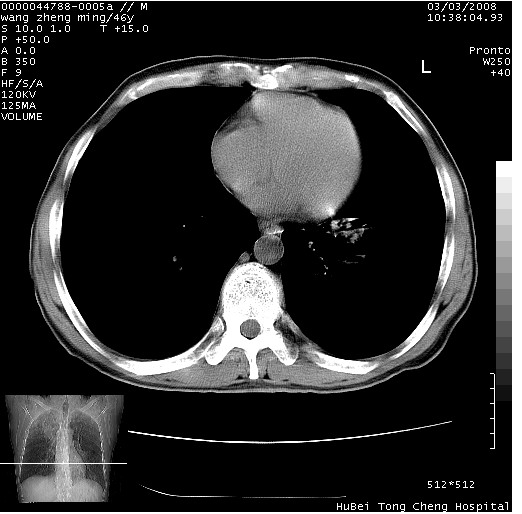

以下是引用卜一在2008-3-22 1:37:00的发言:[br]右肺实质性肿块,边缘不整,明显见毛刺征 分叶征及胸膜凹陷征,右上叶支气管明显变窄,远端散在的片状 斑片状实变影。另:左肺门较大肿块,支气管受累 变窄,远侧见阻塞性肺炎。纵隔内见肿大淋巴结。多考虑:右肺周围性肺癌伴左肺门 纵隔淋巴结转移!